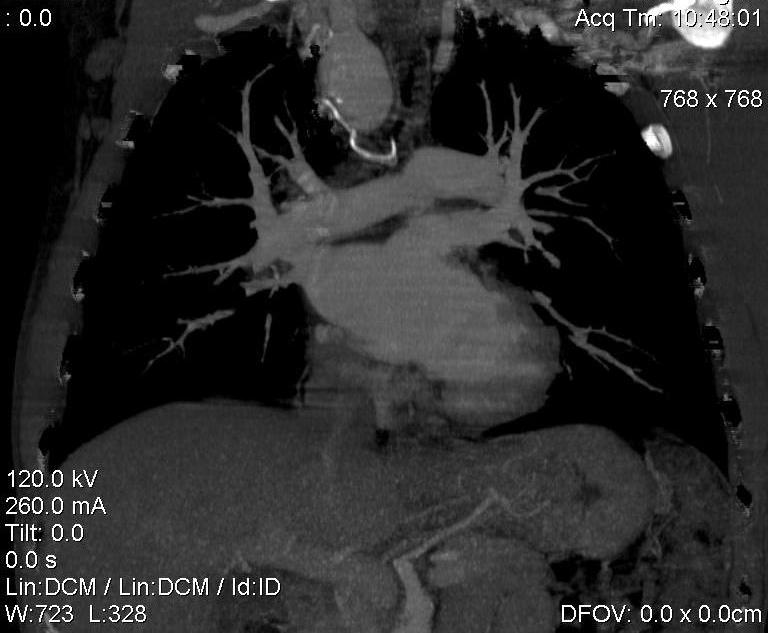

Пациент был направлен на КТ после рентгенографии ОГК, с направительным диагнозом: объёмное образование верхнего средостения.

это аномально расположенная грудная аорта

Конечно, дуга аорты идёт справа от позвоночника (декстра позиция); но есть и ещё одна аномалия той же группы: